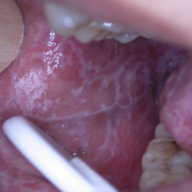

Exemples de cas cliniques :

Récurrence herpétique / Leucoplasie tabagique / Carcinome épidermoïde / Lichen plan / Pathologie bulleuse

Les pathologies de la muqueuse orale sont fréquentes en pratique quotidienne, mais leur diversité d’aspects cliniques, leur évolution parfois trompeuse et la similitude entre certaines lésions rendent leur identification difficile. Les praticiens peuvent se trouver en difficulté pour poser un diagnostic précis, évaluer la gravité d’une lésion, ou choisir la conduite à tenir adaptée, ce qui peut retarder la prise en charge ou l’orientation du patient.

Cette formation d’une journée a pour objectif d’aider les praticiens à mieux reconnaître et prendre en charge les pathologies de la muqueuse orale. Elle vise à leur permettre d’identifier et de décrire les lésions élémentaires de la cavité orale, d’adopter une démarche diagnostique structurée, de reconnaître les principales pathologies courantes comme le lichen oral et les stomatites virales, et d’améliorer leur prise en charge clinique…